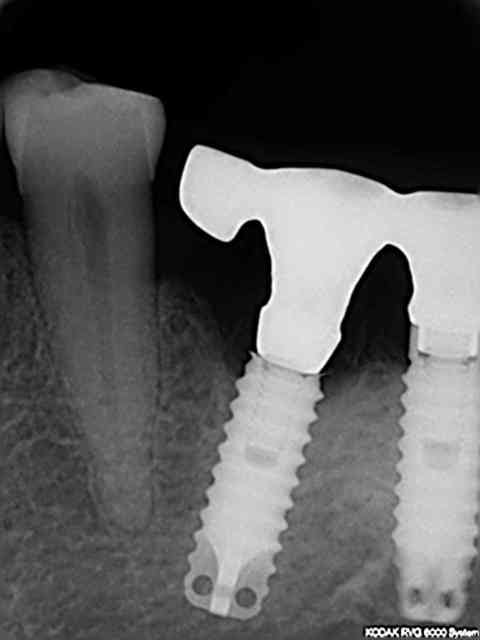

oui bien sur , mais option 2

1-lambeau on vire le col cassé

2-on enlève la vis cassée

3-on réalise une empreinte avec transfert modifié

4-suprastructure transvissée solidarisée entre implants

5-bridge provisoire par dessus

6-réalisation de la suite du traitement initalement prévu (3 implants dans l'autre secteur)

7-équilibration +++

8-wait and see

j'ai décidé de conserver cet implant car longueur+++ évent dans le fut +++ crète fine donc gros dégats lors de la dépose tourne à gauche , ou trépan les dégats seront idientiques avec risque de laisser l'extrémité apicale et nécesité de greffe par la suite...

déja six mois de fonction à suivre

en regardant la rvg avec le col cassé on s'aperçoit que le filetage va bien plus loin que la vis donc j'ai présumé que je pourrai visser plus loin dans le fût.

en supprimant l'octogone du transfert totalement la vis va bien à fond (rvg jointe) mais par contre le transfert n'est pas en butée contre l'implant modifié donc j'ai modifié légèrement la vis pour qu'elle pousse le tansfert contre l'implant (ajout d'un petit anneau de duralay sur les premières spires ) de sorte qu'en vissant on soit bien en butée contre le fût (cf deuxième rvg)

puis j'ai controlé lors de l'essayage de l'armature que l'ensemble soit vraiment passif.